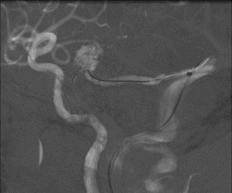

术后造影见AVM已经完全栓塞。